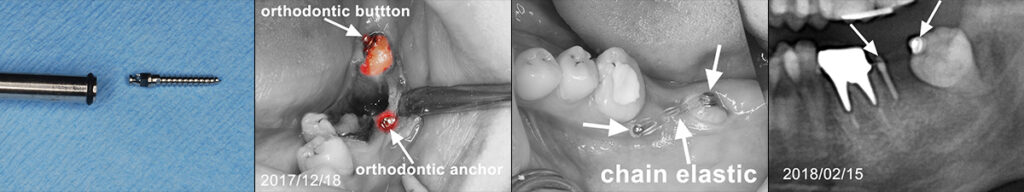

世代が上がれば後方の90度変位した埋伏智歯の移植利用を考えるが歯髄失活は免れないため、困難な矯正であるが萌出間もない大臼歯として今後を託せる生活歯のまま保存する。 矯正用のアンカースクリューと各種装置を智歯に接着させ、移動の各段階で交換しながら抜歯した第二大臼歯部に誘導する。 第一大臼歯は保存治療後ジルコニアセラミック冠で歯冠修復し約7年経過。 治療期間は 2017/12~2019/03

前方大臼歯抜歯時に矯正用アンカーを歯槽骨にねじ込み、引張用のアタッチメントを智歯歯冠に接着